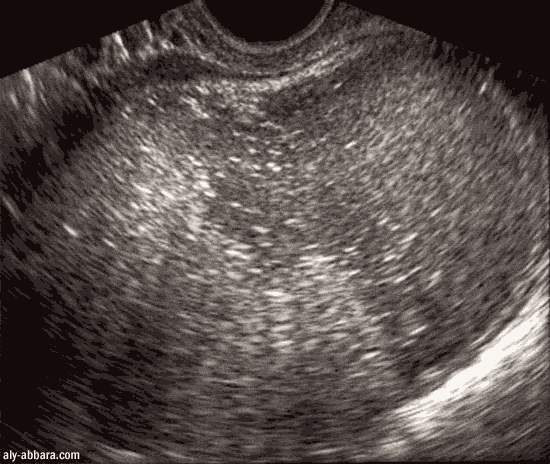

Kyste dermoïde de l'ovaire (tératome bénin)

Sur cette coupe du kyste on voit les deux composantes du kyste :

un magma de poils et une collection d'un liquide graisseux sébacé